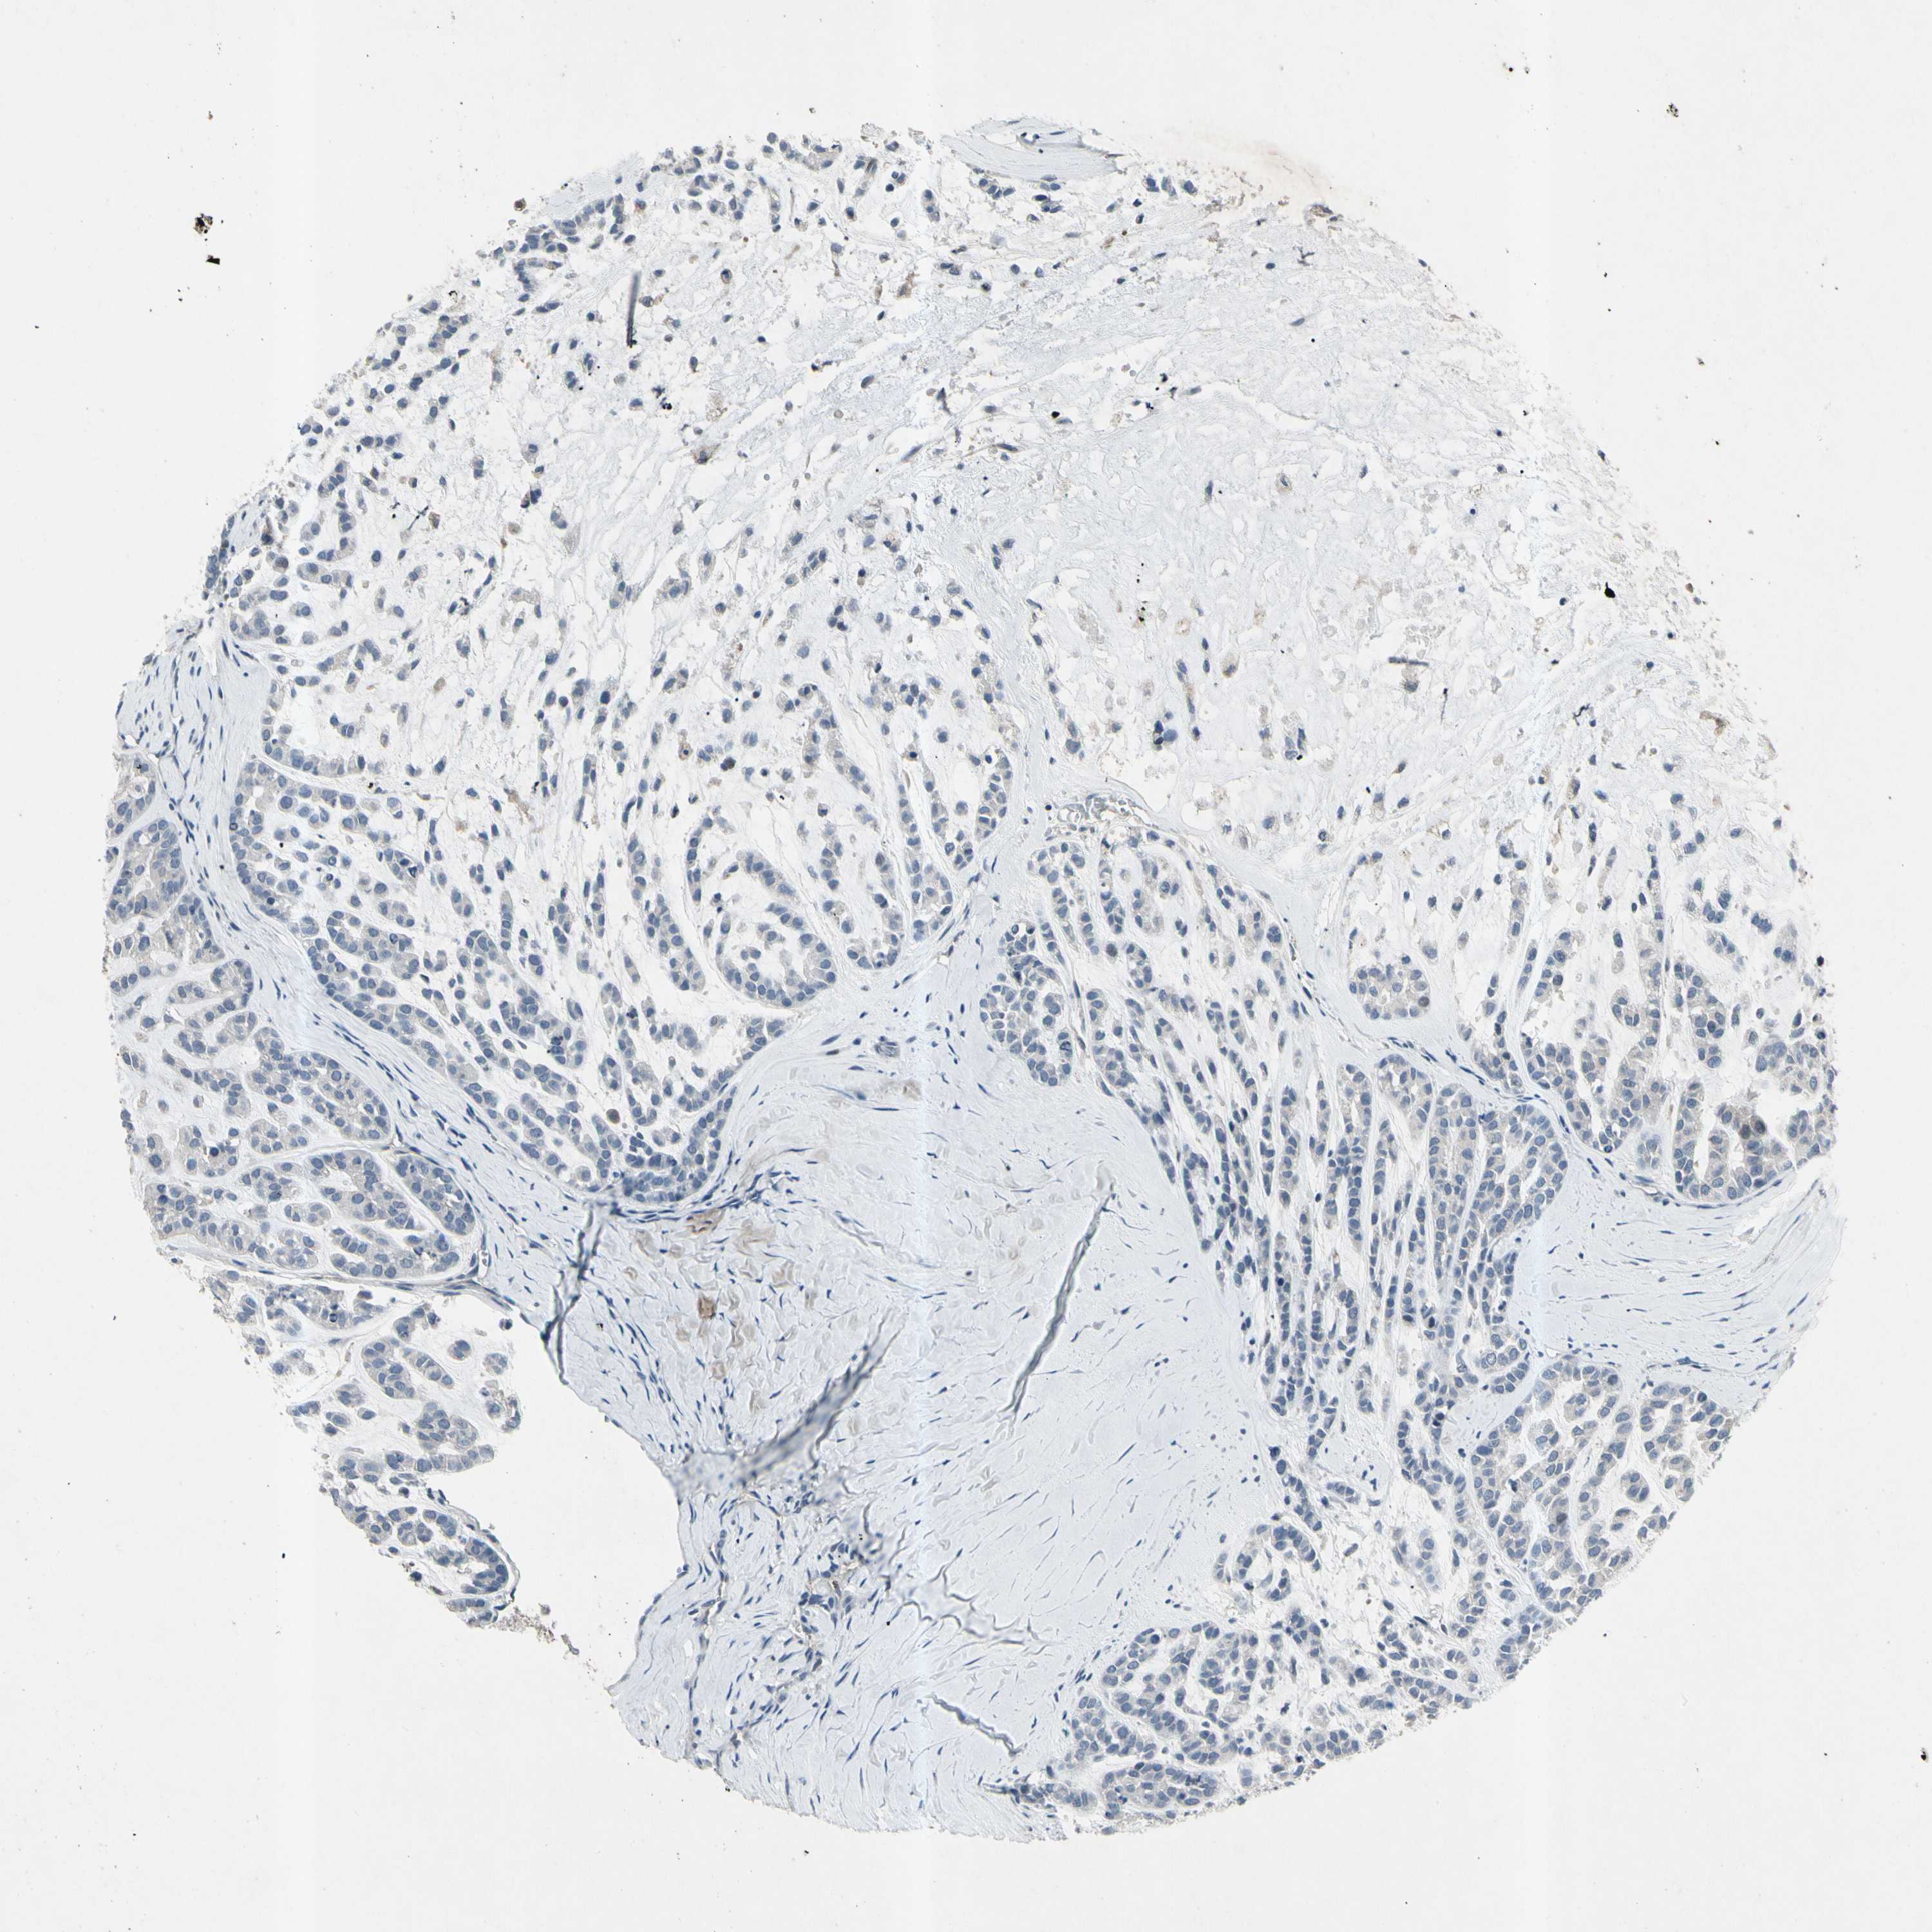

HEAD AND NECK CANCER - Protein expressioni

A mouse-over function shows sample information and annotation data. Click on an image to view it in a full screen mode. Samples can be filtered based on level of antibody staining by selecting one or several of the following categories: high, medium, low and not detected. The assay and annotation is described here.

Antibody stainingi

Antibody staining in the annotated cell types in the current human tissue is reported as not detected, low, medium, or high, based on conventional immunohistochemistry profiling in selected tissues. This score is based on the combination of the staining intensity and fraction of stained cells.

Each image is clickable and will lead to virtual microscopy that enables deeper exploration of all samples and also displays staining intensity scores, fraction scores and subcellular localization as well as patient and tissue information for each sample.

Antibody HPA008588

Staining

High

Medium

Low

Not detected

Intensity

Strong

Moderate

Weak

Negative

Quantity

>75%

75%-25%

<25%

None

Location

Nuclear

Cytoplasmic/membranous

Cytoplasmic/membranous,nuclear

Squamous cell carcinoma, NOS